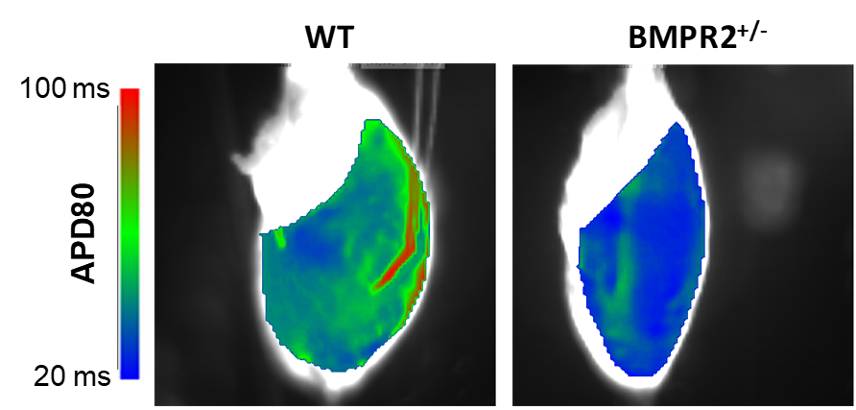

- Investigation of right heart alterations in adult transgenic animals carrying a BMPR2 (Bone Morphogenetic Protein Receptor 2) mutation, under both physiological conditions (normoxia – see Figure 1) and pathological conditions (PH induced by chronic hypoxia). Collaboration with Team 3 of the unit.